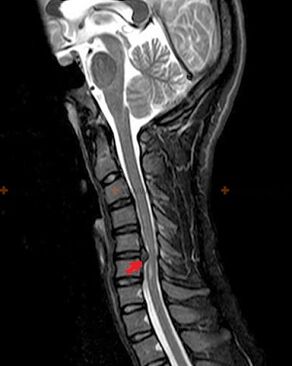

Diagnóstico e signos de raios X

A osteocondrose é un diagnóstico de raios X, xa que só está dispoñible unha imaxe clínica detallada no momento da exacerbación, mentres que os cambios na columna vertebral poden ocorrer co benestar subxectivo completo dunha persoa. Sen un exame de raios X, só podemos falar de sospeita de osteocondrose, porque síntomas similares poden ser causados por outras enfermidades (miosite, neoplasias vertebrales e outras).

Para diagnosticar a osteocondrose utilízanse os seguintes métodos de investigación: radiografía (preferentemente con probas funcionais), MSCT e resonancia magnética. Este último estudo é o máis preferible debido ao feito de que permite visualizar moi claramente o estado das estruturas intervertebrais.

Os signos de raios X da osteocondrose inclúen os seguintes cambios na columna vertebral:

- Altura reducida dos discos intervertebrais.

- Presenza de crecementos óseos marxinais.

- Violación da localización das vértebras entre si.

- Deformacións de corpos vertebrales e arcos, etc.

A presenza dos cambios descritos anteriormente, así como os cambios na estrutura do disco intervertebral, detectados por MSCT e resonancia magnética, serven como signos fiables que confirman a presenza de osteocondrose.